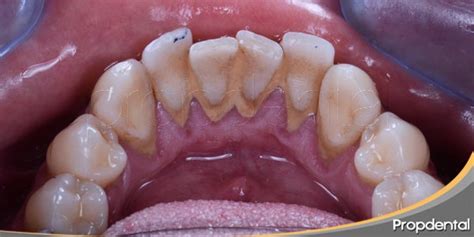

El sarro es, por tanto, resultado del endurecimiento de esa placa bacteriana no retirada. Forma un recubrimiento blanquecino o amarillento en la base de los dientes, en especial en los dientes inferiores anteriores por el lado de la lengua y en los molares superiores por el lado de la mejilla.

El sarro tiene la apariencia de una costra gruesa que cubre los dientes, sobre todo la parte trasera de las piezas delanteras inferiores, que es una zona más difícil de limpiar. También puede formarse entre las piezas dentales y el borde de las encías.

Inicialmente su color es blanquecino, pero se mancha con facilidad y puede adquirir un tono amarillento o amarronado. Asimismo, puede presentarse acompañado de hinchazón y enrojecimiento de las encías, cuadro conocido como gingivitis.

En función de su localización, el sarro puede ser:

- Supragingival: Se acumula en la superficie visible de los dientes y encías.

- Subgingival: Se localiza por debajo de la línea de la encía, por lo que es más difícil de percibir.